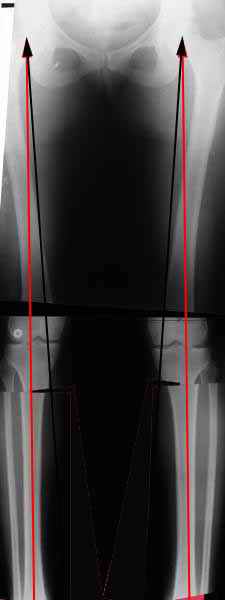

Вот, с учетом и без учета, и на разных уровнях...